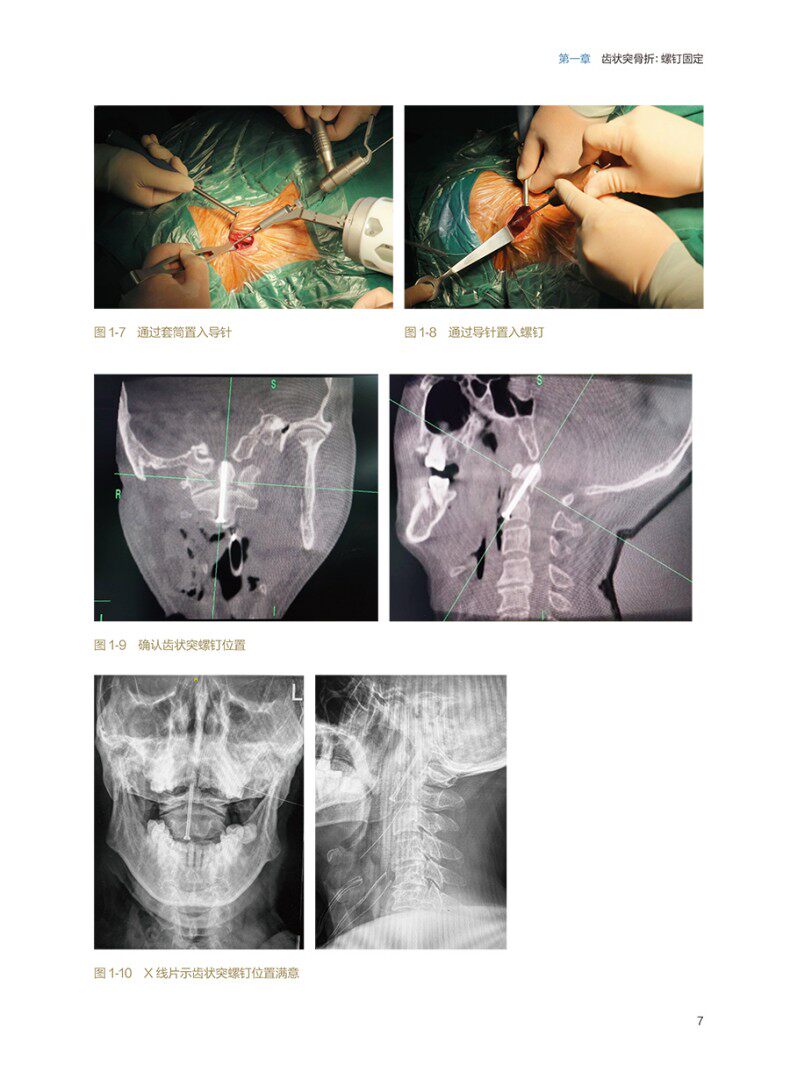

机器人基本是通过影像系统进行术前/术中规划和实时导航,使用多自由度机械臂进行操作,不仅可以帮助外科医生实现更高的手术精确度,还可以消除某些人为操作失误、提高手术效率、减少术后并发症。本书共包括前言及五个章节,主编团队以机器人骨科手术病例为核心内容,对机器人辅助骨科手术的使用方法、技巧及常见术式等进行归纳总结及概述,内容覆盖了颈椎、胸腰椎、骨盆、四肢、足踝等五章。编排注重实用,聚焦具体病例,对术中的具体操作进行专业解读与介绍,文字讲解配合相应图片,图文并茂的展现了手术技术的具体步骤。同时还介绍了笔者的使用经验心得,有助于指导读者实操 ,较好的掌握和执行骨科机器人手术。